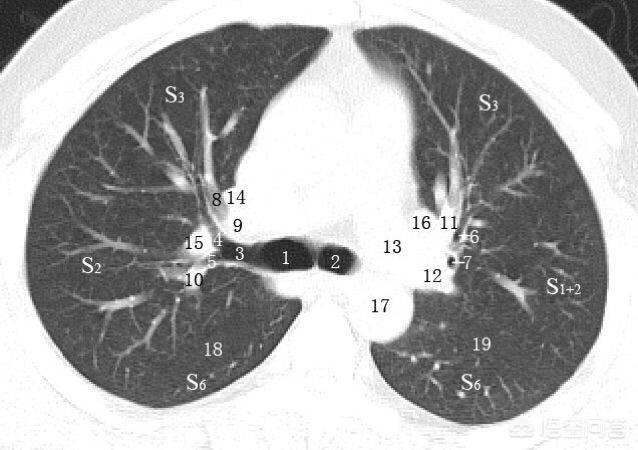

如图所示,气管从喉咙下来,大约在第6胸椎水平左右分叉,伸入肺脏,并且像树枝一样越分越细,最终到达末梢的肺泡。所以气管和支气管是空气进入肺脏的通道。

气管和肺泡腔都是空气,密度很低,所以在CT上呈黑色。如上图中的1-7,就是左右主支气管和它的分支,呈黑色,像树枝一样越分越细,所以也被称为支气管树。

我们知道,肺里有两套重要的管状结构:一套是支气管树,让空气进入肺脏;另一套是血管系统(肺动脉和肺静脉),让人体的血液和空气完成血氧交换,吸收氧气,呼出二氧化碳

所以白色的条形影是肺里的血管,其中肺动脉跟支气管伴行,也是越分越细,在肺泡壁形成毛细血管网,通过血红蛋白氧合吸收、转运氧气,同时析出二氧化碳。完成血氧交换之后,毛细血管再逐渐汇总,越来越粗,构成各级肺静脉,回到左心房-左心室,进入到体循环,供应全身的氧气。